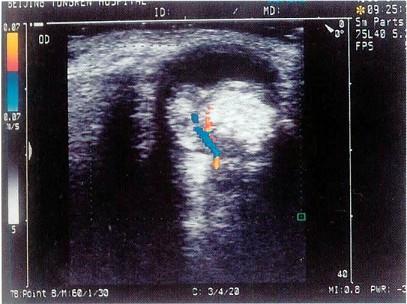

问题 患者,3岁,发现瞳孔区黄白色反光。眼底检查发现玻璃体浑浊。结合超声声像图,最可能的诊断是?(?)

选项 A.视网膜母细胞瘤 B.新生儿视网膜脱离 C.原始玻璃体增生症 D.先天性白内障 E.玻璃体后脱离

答案 A